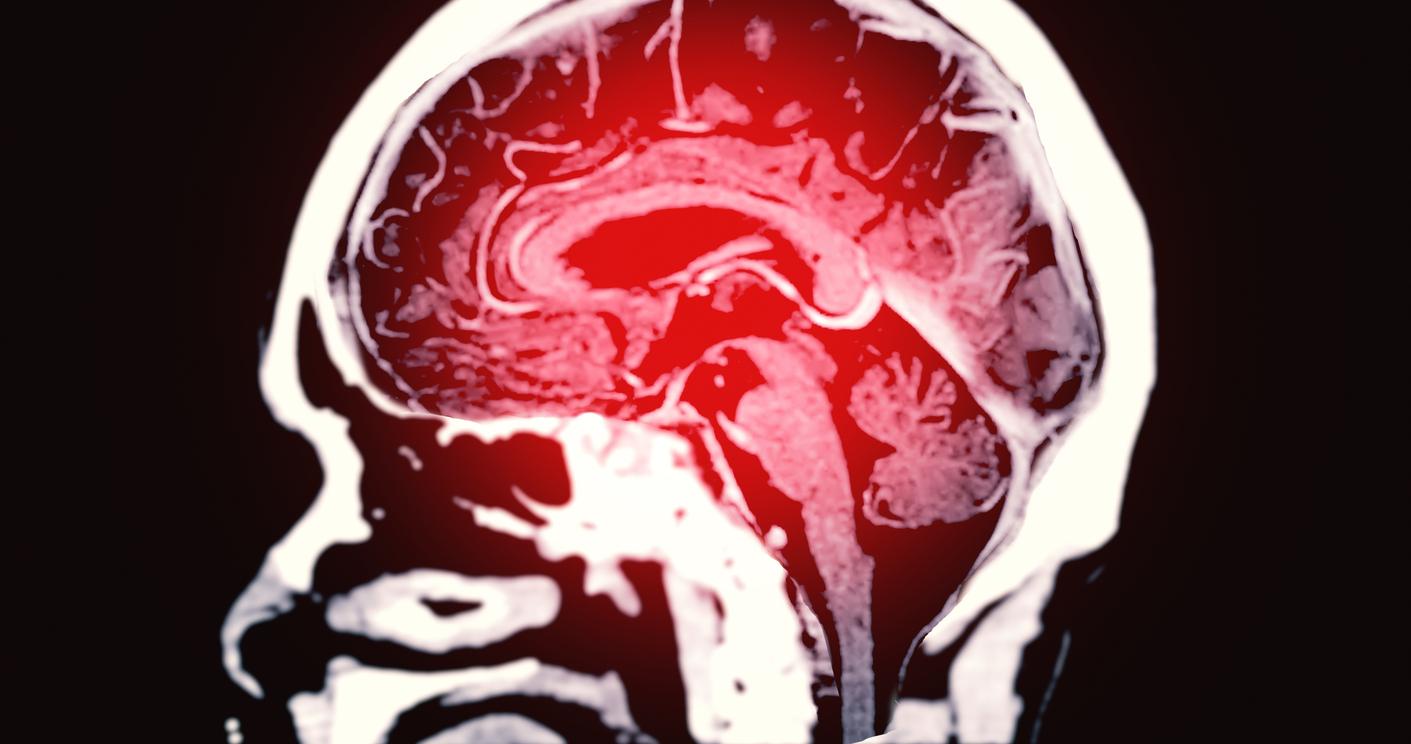

Les formes les plus graves des accidents vasculaires cérébraux (AVC) aboutissent à des handicaps sévères, un besoin constant de soins infirmiers ou encore au décès. Dr Catriona Reddin de l’Université de Galway et son équipe ont tenté de déterminer les facteurs qui augmentent le risque de souffrir de ce type d’attaque cérébrale.

Leurs travaux, publiés dans la revue Neurology le 13 novembre 2024, révèlent que l'hypertension artérielle, la fibrillation auriculaire et le tabagisme sont les plus gros contributeurs aux AVC graves.